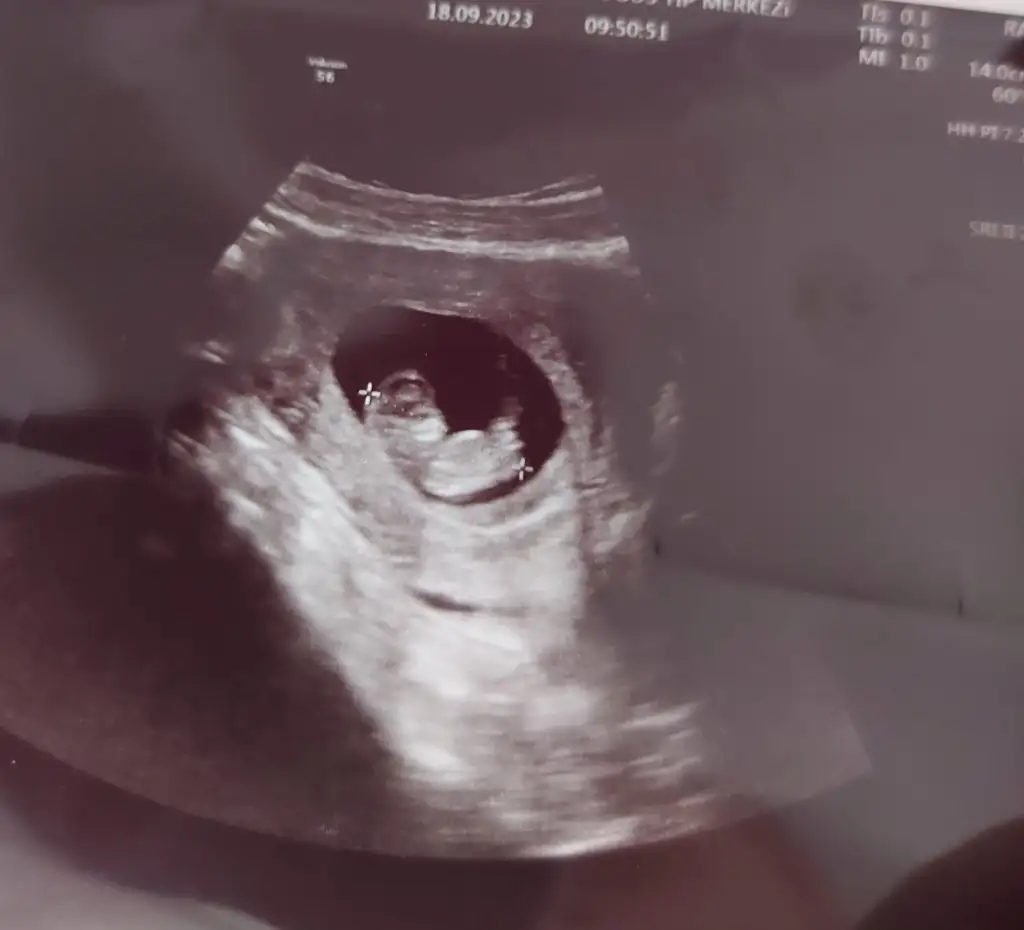

Merhaba bana da yorum yapabilir misiniz? Karından ultrason 10+2 burda 🌸

İyi akşamlar burada 10 hafta 3 gün gözüküyor ultrasona göre sizde saniyeye belli mi ?

Karından ultrason bu arada